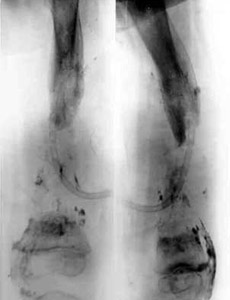

Results of treatment.